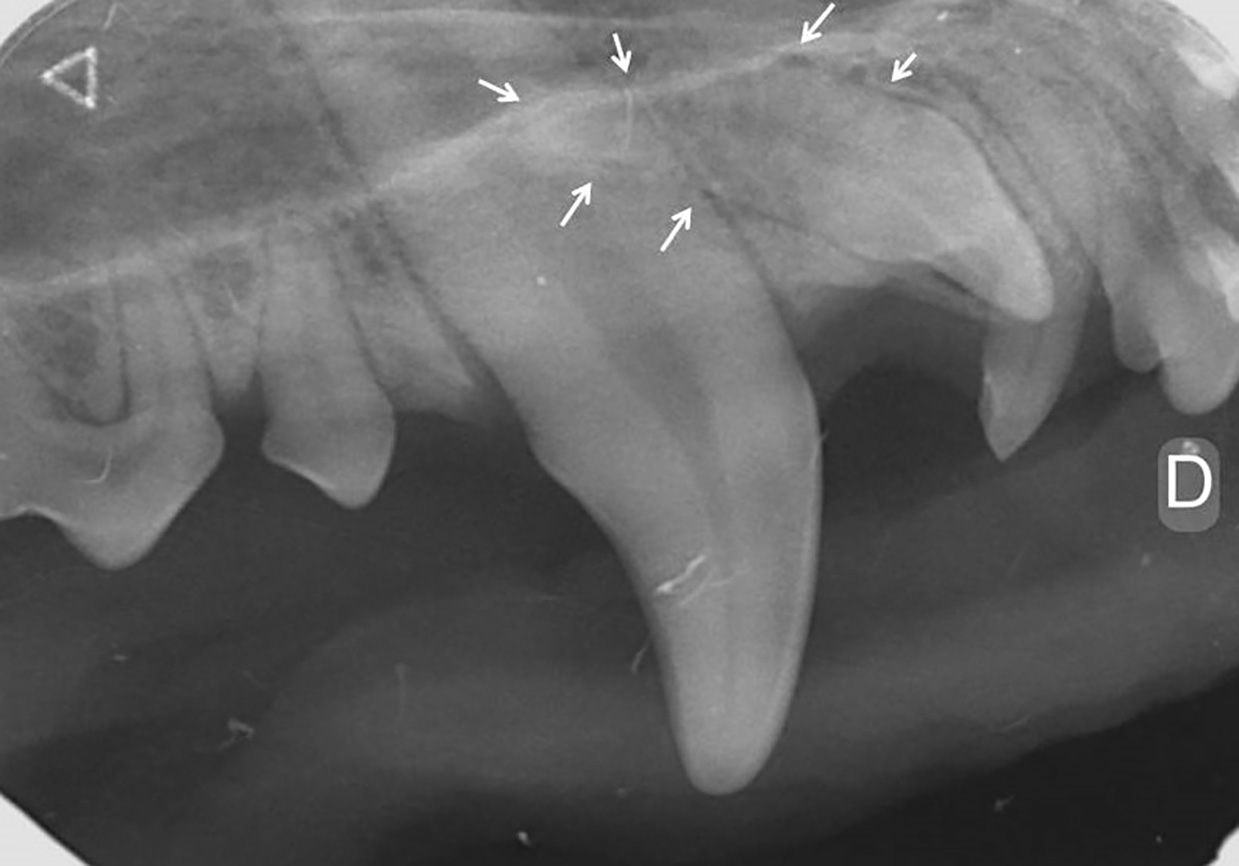

Para el diagnóstico de la EP, además de realizar un examen periodontal a través del sondaje debemos apoyarnos en la radiografía, ya que nos proporciona información acerca de la cantidad de pérdida ósea existente, así como del patrón que sigue esta pérdida (horizontal y/o vertical). En dientes multirradiculares, podemos servirnos de la furca para evaluar la pérdida de hueso, ya que aparecen áreas radiolúcidas bajo la bifurcación radicular a medida que se produce la destrucción ósea.

De acuerdo a esta pérdida del hueso alveolar detectada a nivel radiológico, clasificaremos la EP en cuatro grados:

- Grado 1 (PD1): sin pérdida ósea.

- Grado 2 (PD2): pérdida del soporte óseo menor al 25 % (imagen 7).

- Grado 3 (PD3): pérdida del soporte óseo de un 25-50 % (imagen 8).

- Grado 4 (PD4): pérdida del soporte óseo mayor de un 50 % (imagen 9).